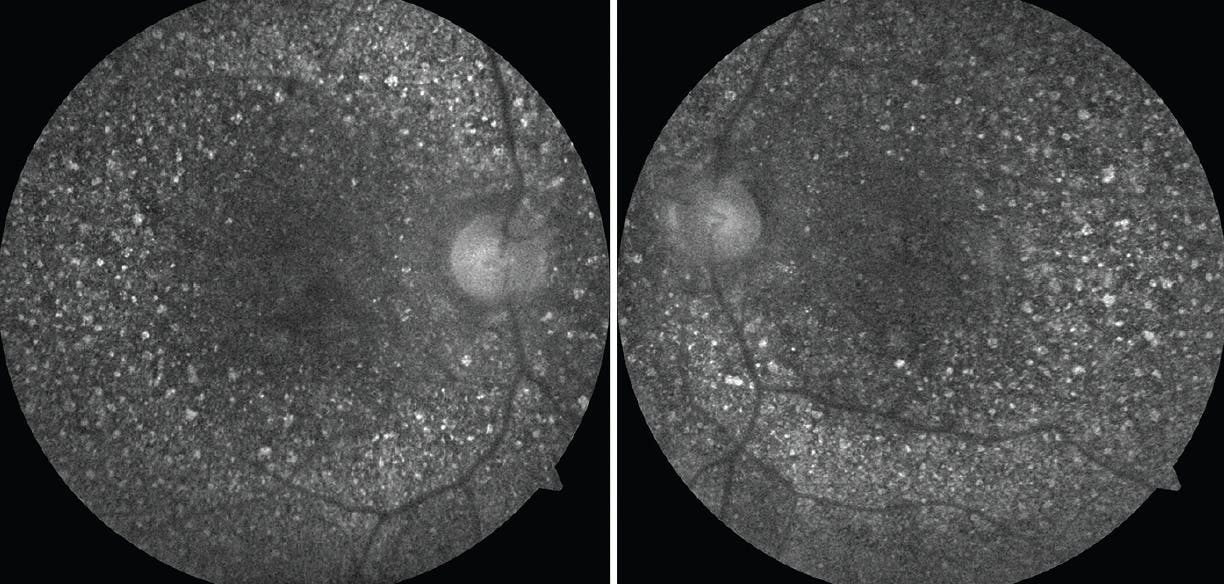

The anterior segment examination of each eye was unremarkable. Color fundus photography revealed diffuse, glistening, yellow-white crystalline deposits at the posterior pole of the retina in each eye (Figure 1). Fundus autofluorescence (FAF) also showed hyperautofluorescent deposits at the posterior pole of each eye (Figure 2).